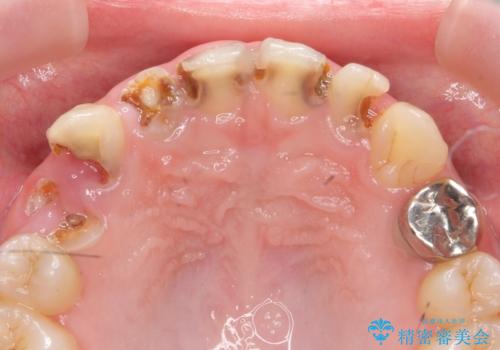

[滑舌を治したい] 舌の小帯の形成術

- ベロの動きが制限され、滑舌が悪いので改善したい。と舌小帯の形成術を希望され来院されました。

10分程度の小手術を行うことで滑舌の改善を図ります。

大幅に舌の動きが良くなり、滑舌がよくなったと喜んでいただくことができました。